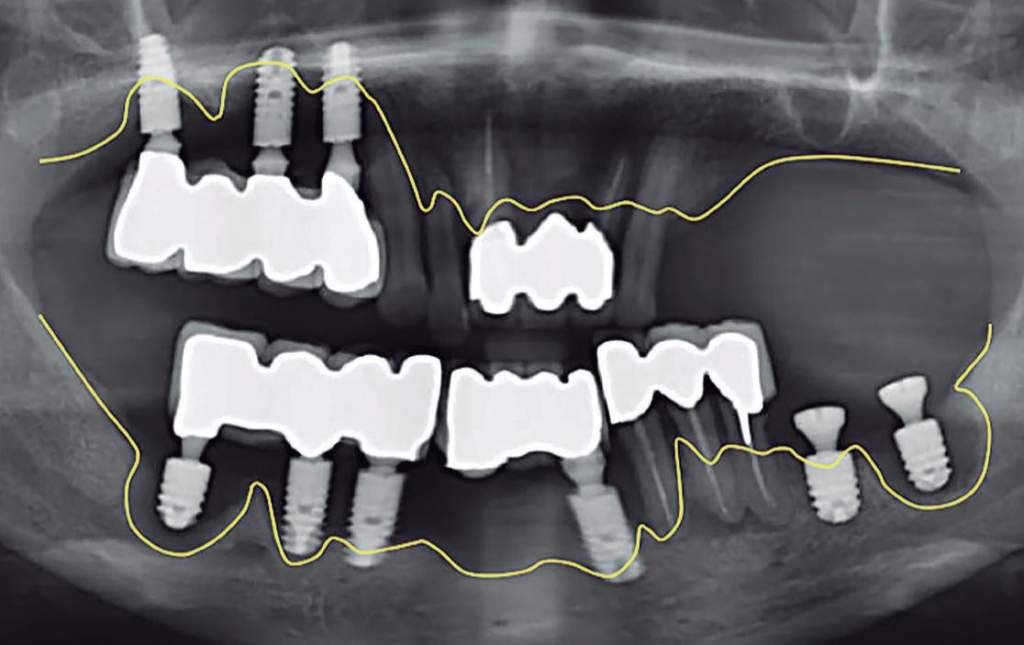

下圖是一位來診所尋求協助的患者的口腔X光片,他植牙初期非常穩固,牙醫師才協助製作假牙,後來家裡發生一些變故,患者陷入嚴重憂慮與煩惱,最後這些植體竟在短短幾個月的時間內,因相當於地基的齒槽骨頭流失而變得不堪使用,可見過度耗氧,身體嚴重酸化後,全身骨頭會慢慢溶解,影響真的不容小覷。